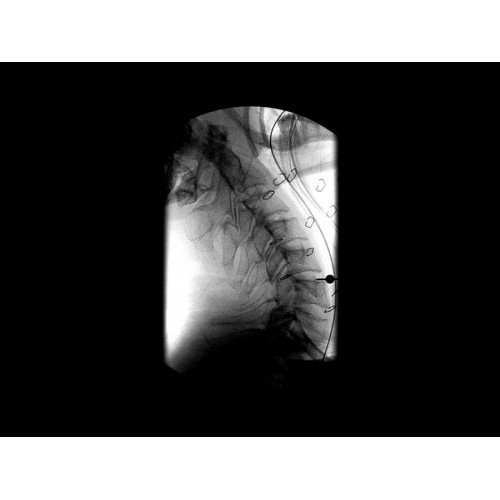

GE Brivo OEC 785/865 оснащен инновационной системой обработки изображений, которая обеспечивает четкую визуализацию в реальном времени. Система автоматически адаптирует параметры исследования под конкретную хирургическую задачу, обеспечивая оптимальное соотношение качества изображения и лучевой нагрузки. Особое внимание уделено эргономике работы хирургической бригады.

В практической работе GE Brivo OEC 785/865 демонстрирует стабильно высокое качество визуализации, что особенно важно при проведении сложных малоинвазивных вмешательств. Оборудование позволяет сократить время процедуры и повысить ее безопасность для пациента. Многие хирурги отмечают удобство работы с системой и ее надежность в интенсивной эксплуатации.